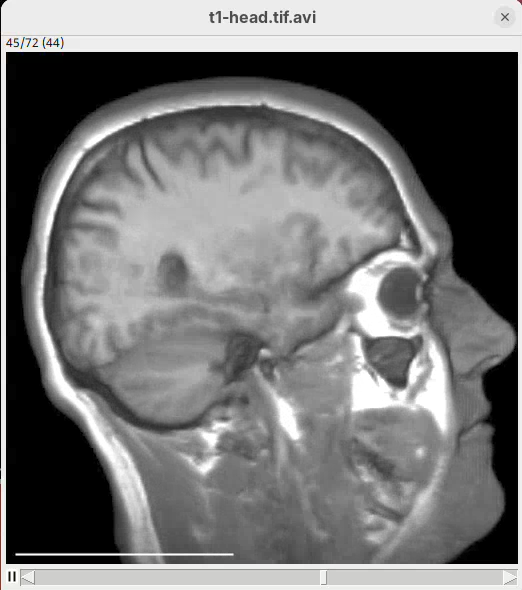

The left head is the one without easing (linear transition) and the right head is the animation with easing. Note how the right head accelerates the rotation at the beginning, turning much faster, and then decelerates towards the end of the rotation. Both end the rotation at the same time. Play both animations side-by-side to see the difference (it’s very clear, once you see it).

From frame 0 to frame 35 rotate by 360 degrees horizontally

From frame 36 to frame 71 change channel 1 bounding box min z to 60

From frame 72 to frame 99 change channel 1 bounding box min z to 0- Press

Run.

The script is saying to rotate 360 degrees horizontally, as before, set the Z range minimum to 60 (roughly halfway through the sample) for about 30 frames, and then set the Z range minimum back to 0 in the subsequent 30 frames. And that’s what we get.